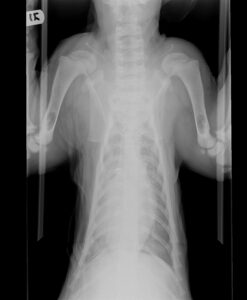

Last week the cubs received their final vaccines as kittens until they turn a year old. X-rays were taken to get an overall perspective of their health and these tigers are as perfect as they seem. From their teeth and gums, eyes, ears and

paws, these little tigers are in top shape! During their wellness visit, the veterinary staff also took the opportunity to get some colorful paw prints of the cubs that may be available for purchase soon.